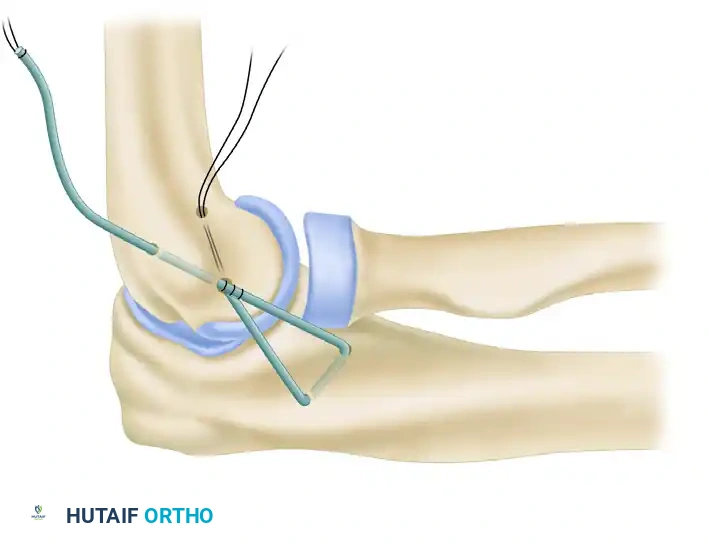

Before graft placement, the native, attenuated tissues are managed. Perform an imbrication and advancement of the ulnar band of the radial collateral ligament and the radial part of the radial collateral ligament. This is accomplished using a Bunnell suture technique, placing the sutures through drill holes at the anatomical origin of the ligament in the humerus. This plicates the posterior and anterior capsule, providing a robust secondary restraint.

4. Ulnar Tunnel Preparation

Attention is now turned to the ulna. The ulnar tunnel must be placed precisely in the crista supinatoris tubercle.

* Using a high-speed burr or a 3.2-mm drill, create two converging drill holes at the supinator crest.

* The holes should be separated by a 1.5 to 2.0 cm bone bridge to prevent cortical blowout during graft tensioning.

* The tunnel is oriented to have optimal alignment with the isometric point on the lateral epicondyle.

5. Graft Harvest and Passage

The palmaris longus tendon is the graft of choice due to its accessibility and biomechanical properties. If absent, a strip of triceps fascia or a gracilis autograft may be utilized.

* Harvest the graft and prepare the ends with running locking sutures (e.g., #2 non-absorbable suture).

* Pass the graft through the prepared ulnar tunnel.

* Create a "yoke stitch" to secure the graft upon itself at the ulnar insertion, ensuring a low-profile and secure anchor point before passing the limbs proximally toward the humerus.

6. Humeral Tunnel Preparation and Isometry

Identifying the isometric point on the lateral epicondyle is paramount.

* A tunnel is made in the humerus at the isometric origin.

* The primary entry hole is expanded in a posterosuperior direction to emerge posterior and superior to the point of isometry.

* A second humeral tunnel is drilled to exit posterior and inferior from the common entry site, creating a V-shaped or Y-shaped intraosseous pathway.